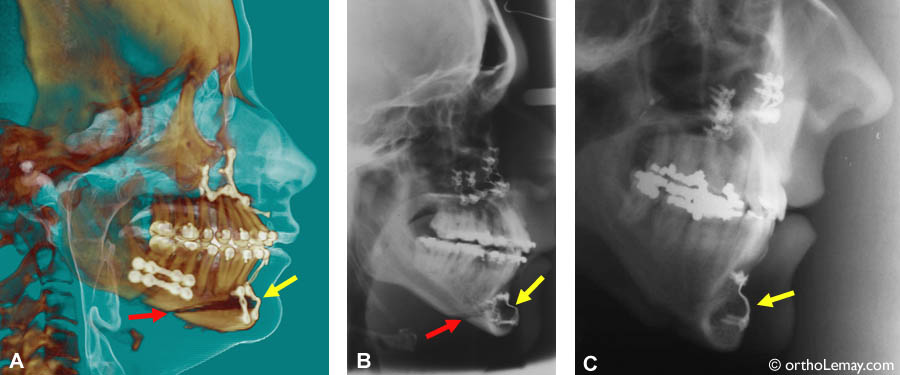

(A, B et C) Des radiographies panoramiques montrent la présence de plaques de fixation chez des patients ayant eu une chirurgie au menton (génioplastie d’avancement ou de recul). (A et B) montrent aussi des plaques utilisées pour immobiliser la mâchoire supérieure suite à une chirurgie et (C) montre des vis à l’arrière de la mandibule suite à un avancement de la mâchoire inférieure.

Radiographies montrant des chirurgies d’avancement du menton. Les flèches rouges indiquent la ligne de coupe. Cette dernière sera remplie par l’os éventuellement. Les flèches jaunes indiquent les plaques de fixation rigides qui unissent les deux segments de l’os du menton pendant la guérison et solidification de l’os.